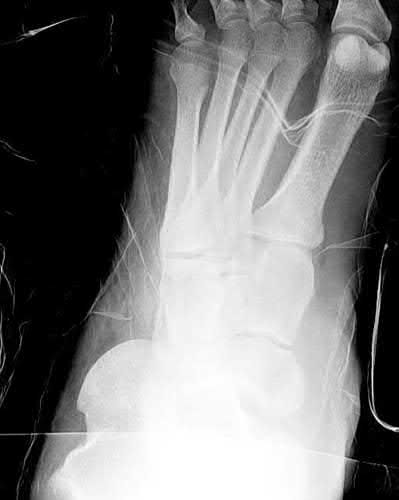

Figure A demonstrates an AP radiograph of a bimalleolar ankle fracture. Figure B demonstrates a lateral radiograph of a bimalleolar ankle fracture.

The patient is a diabetic with poorly controlled blood sugar and peripheral neuropathy presenting with a bimalleolar ankle fracture with a loss to follow-up for 3 months. All of the answer choices are potential complications with nonoperative treatment, but fracture displacement is the most likely to occur.

Ankle fractures in diabetic patients are associated with increased complications compared to nondiabetic counterparts. The glycation damage to cellular

components as well as the decreased blood flow with microangiopathic changes results in substantially decreased bone healing. Patients diabetic comorbidities, such as retinopathy, nephropathy, vasculopathy, and neuropathy have a higher rate of wound complications, deep infections, malunion, nonunion, and Charcot arthropathy. Due to the delayed healing, surgical treatment with supplemental fixation is recommended.

Chaudhary et al. performed a review of ankle fractures in diabetic patients and concluded that diabetic ankle fractures are at high risk for fracture displacement and delayed union, even with surgical treatment. The authors recommend supplemental fixation with external fixation or multiple syndesmotic screws. Postoperatively patients should undergo prolonged immobilization, 2-3 times that of nondiabetics.